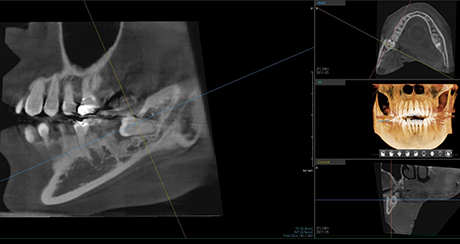

Extraction technique with nerve considerations

Using 3D CT, we evaluate the shape of the wisdom tooth, its roots, and surrounding nerves to support a safer extraction process.